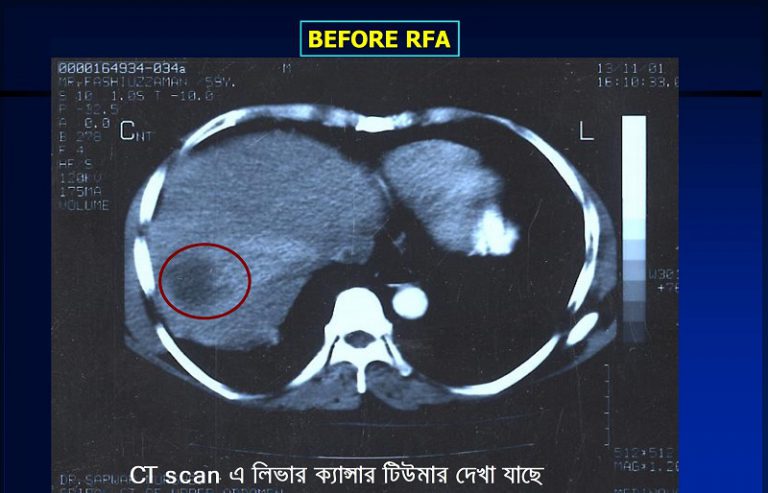

২। RFA (রেডিও ফ্রিকোয়েন্সি এব্লেশন)

২.RFA (রেডিও ফ্রিকোয়েন্সি এব্লেশন)ঃ এই পদ্ধতি ব্যবহারের মাধ্যমে ৫-৬ সেঃমিঃ লিভার টিউমার কে সম্পূন ধ্বংস করা সম্ভন হয় অথচ আশেপাশের সুস্থ কোষের কোন ক্ষতি হয় না। এ পদ্ধতির সফলতার হার ৮৫%-৯৫%। এ কারনে ৫-৬ সেঃমিঃ লিভার ক্যান্সার এর চিকিৎসা হিসেবে সারা বিশ্বে আর এফ এ (RFA) সব চেয়ে বেশি সমাদূত। এর পার্শ্ব প্রতিক্রিয়াও খুবই কম।